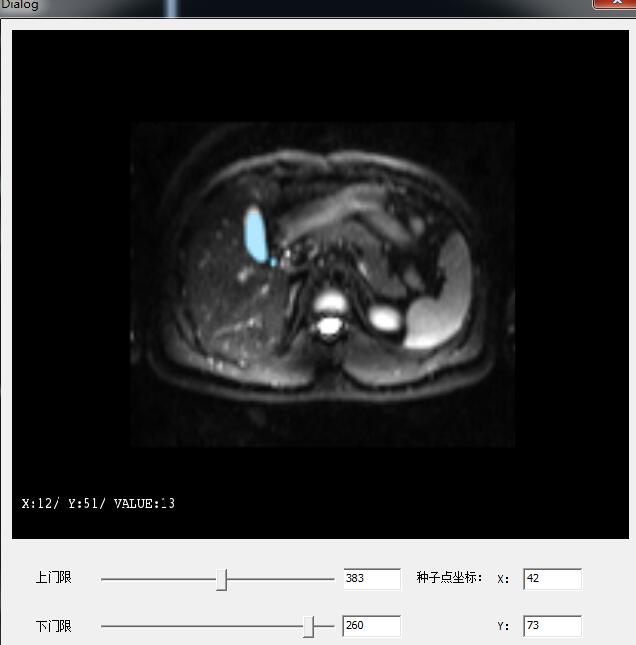

这是在一个博客上看到的效果图,我也想实现这种效果,区域生长的分割算法已经做好了,可是要怎么实现这种显示效果啊?求大神能给一些指导性的意见!多谢多谢!

你好!我现在就是按照吧主的方法一实现了!效果图如下。但是不是在序列里做出来的,是一个二维的单幅图片。但是我用同样的办法,对一个三维的数据块去做,就显示不出来,但是单独显示Mask的结果,是正确的,就是用AddActor加上去之后,就只有原来的,Mask不显示!

对于单幅二维的图像,用了吧主的第一种方案,就是这个效果!

但是如果是序列的三维数据块,Mask就显示不出来!